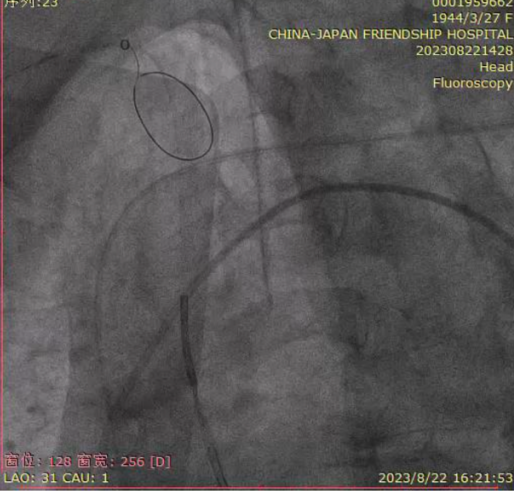

根部造影评估,瓣架底边对齐,左冠显影良好,同轴性一般,瓣膜压缩,锚定良好,瓣下深度4-5mm;

瓣膜脱钩,完成释放,最终造影显示瓣膜形态佳,未见明显反流;

回撤脑保护装置,完成手术。